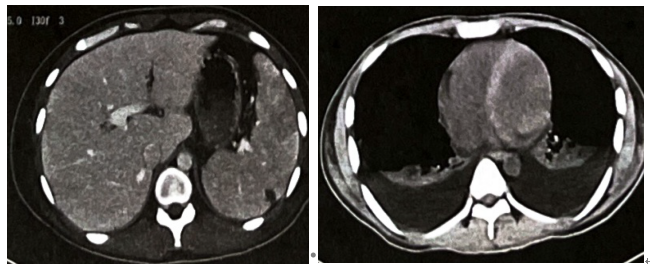

心电图:①窦性心律;②大致正常心电图。胸部CT、上腹部CT平扫及增强扫描:两肺下叶节段性实变膨胀不全并双侧胸水,肝脾大,脾内低密度灶,考虑脾梗死可能,结合病史考虑腹膜炎不除外(图1)。

图1 胸部 CT、上腹部 CT平扫加增强